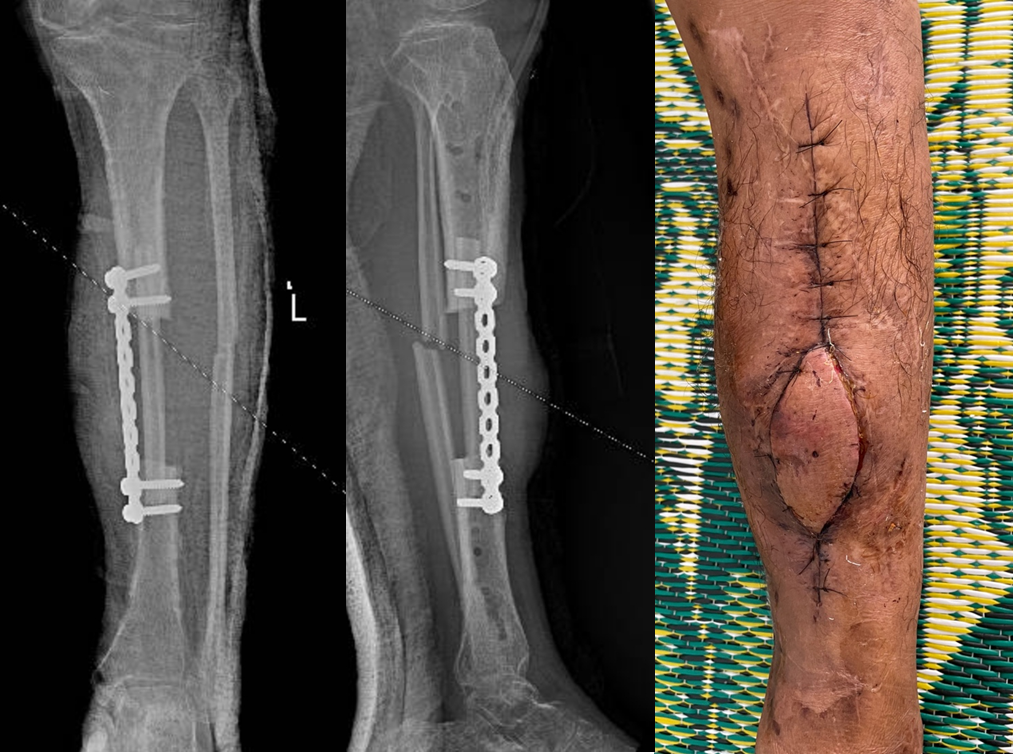

Gãy hở mất đoạn xương đã được cố định ngoài

Đoạn xương mác dài 12cm kèm cuống mạch